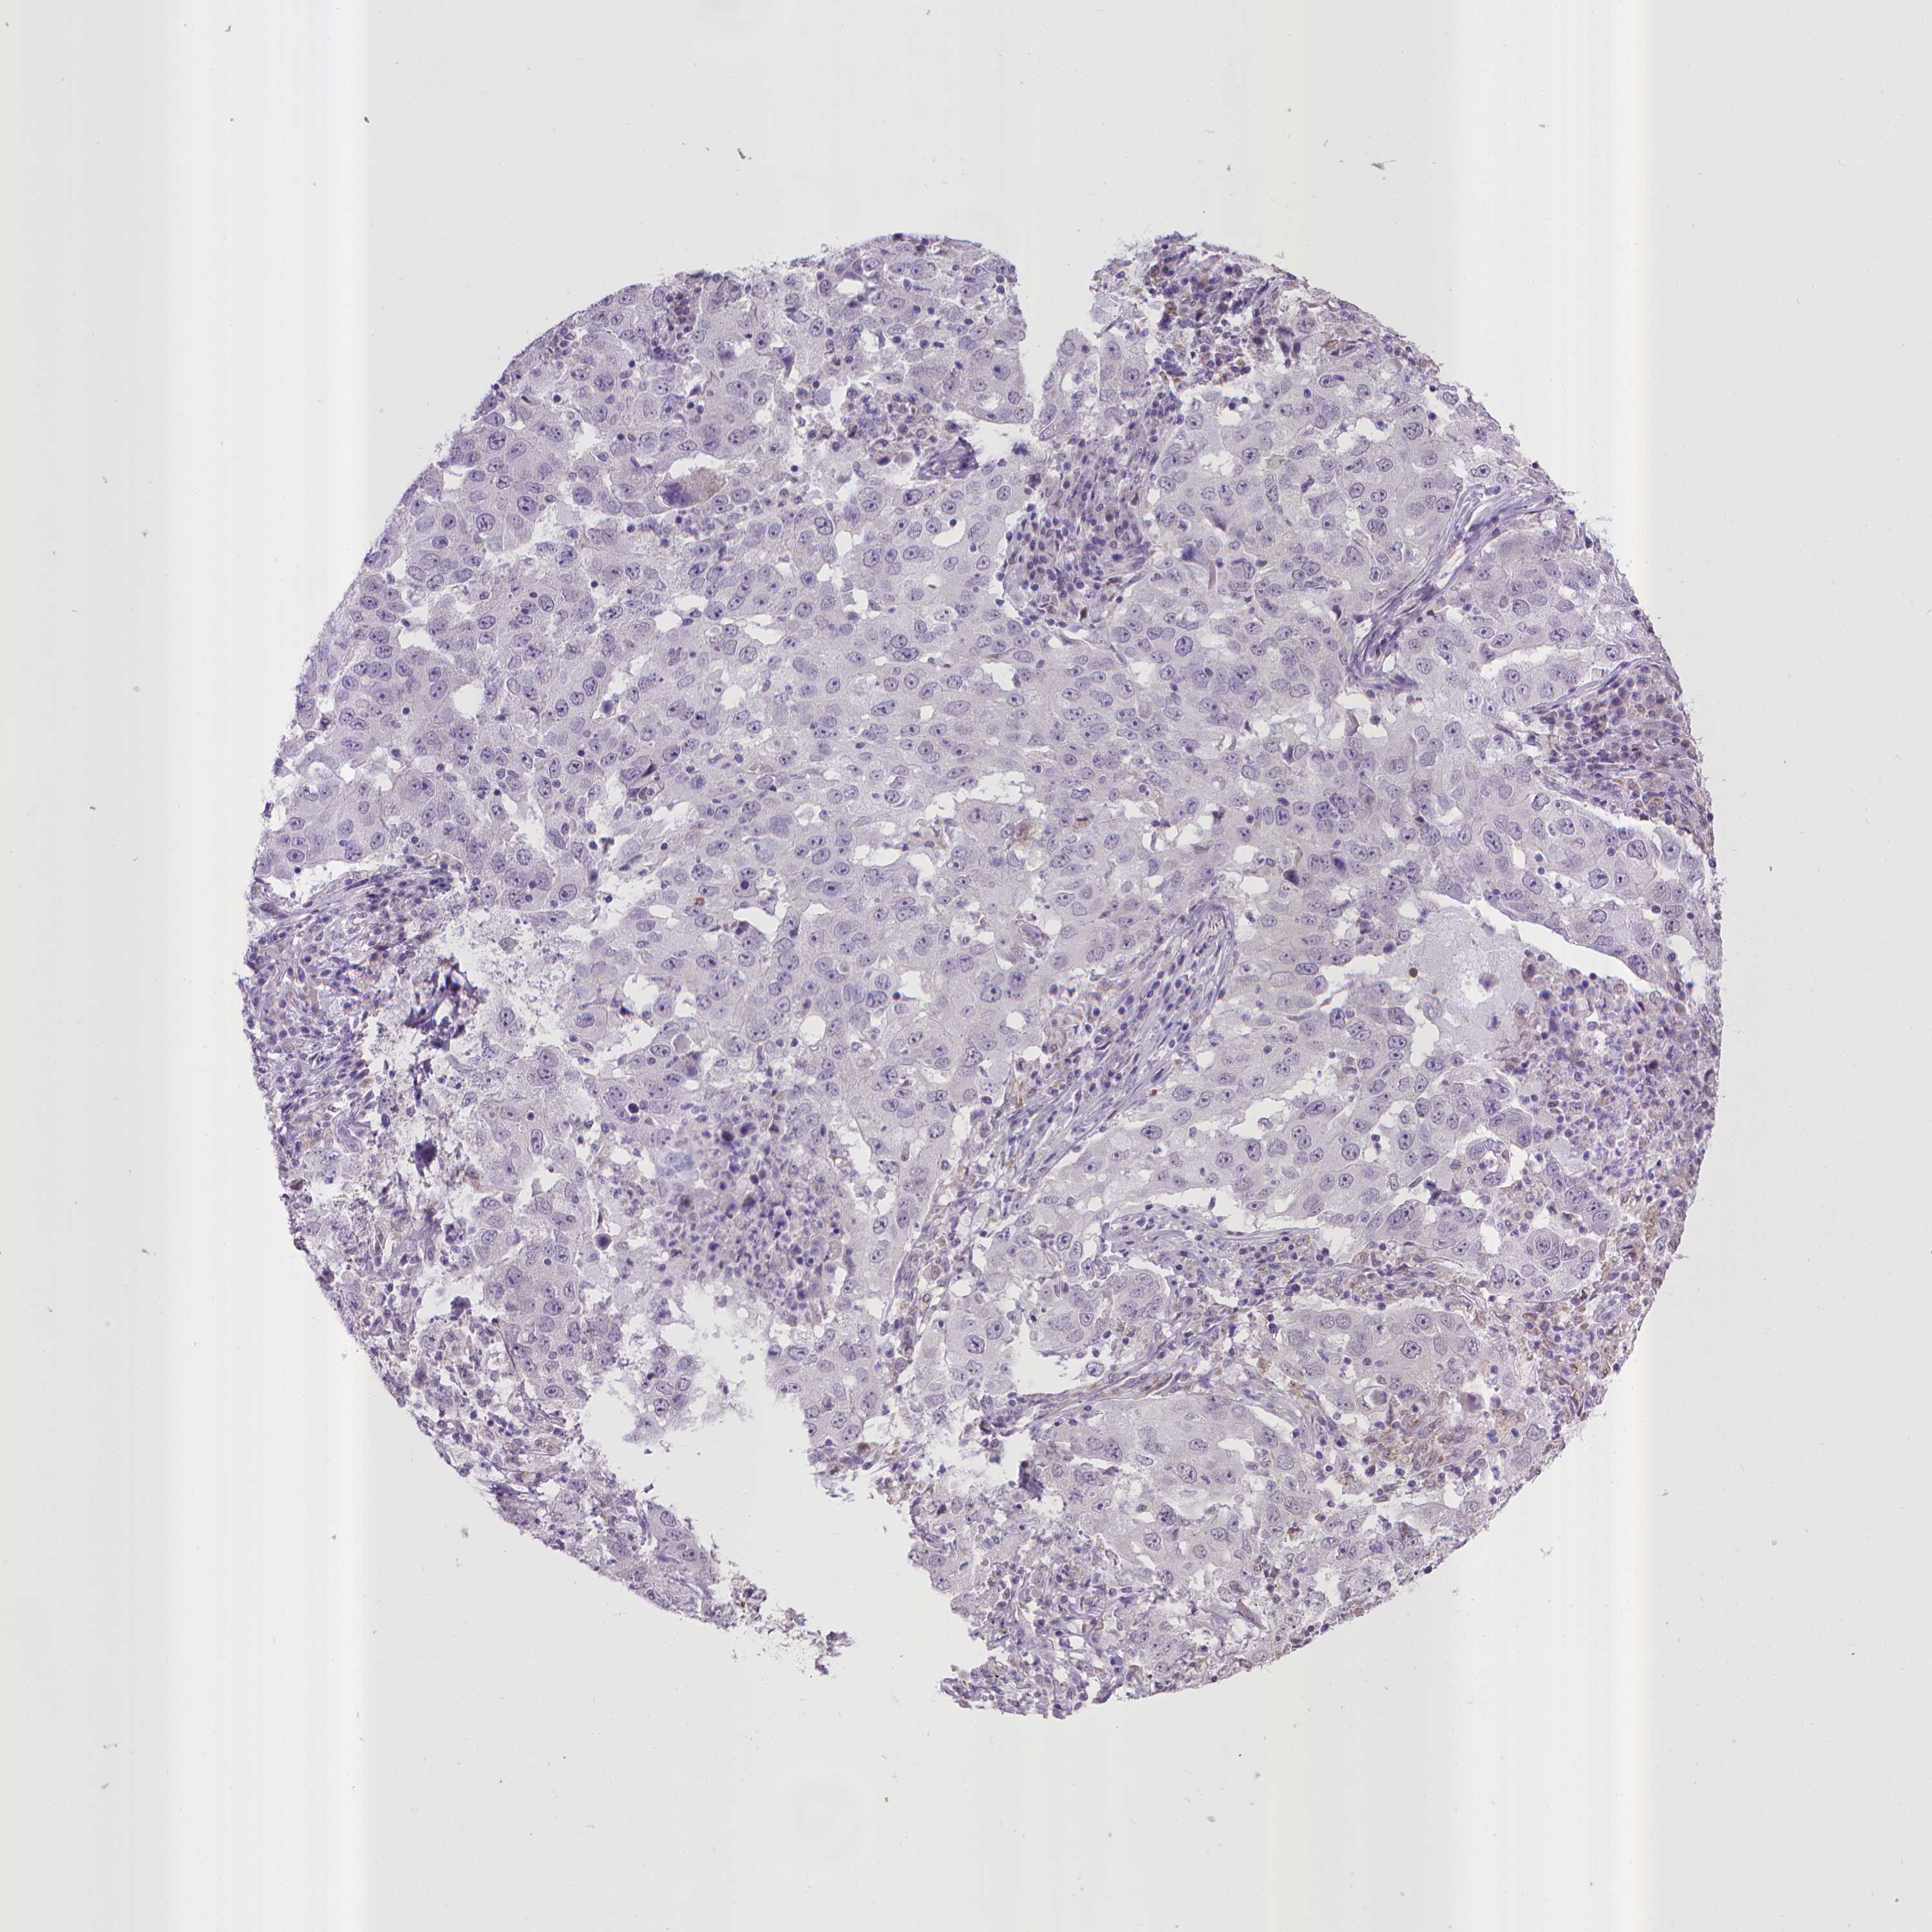

CANCER LUNG CANCER Show tissue menu

LUAD TCGA LUAD VALIDATION LUSC TCGA LUSC VALIDATION PROTEIN LUAD CPTAC PROTEIN LUSC CPTAC PROTEIN EXPRESSION